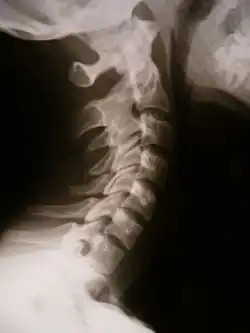

![]() X-ray showing synostosis in the cervical spine | |

Synostosis (plural: synostoses) is fusion of two or more bones. It can be normal in puberty, fusion of the epiphyseal plate to become the epiphyseal line, or abnormal. When synostosis is abnormal it is a type of dysostosis. Examples of synostoses include: